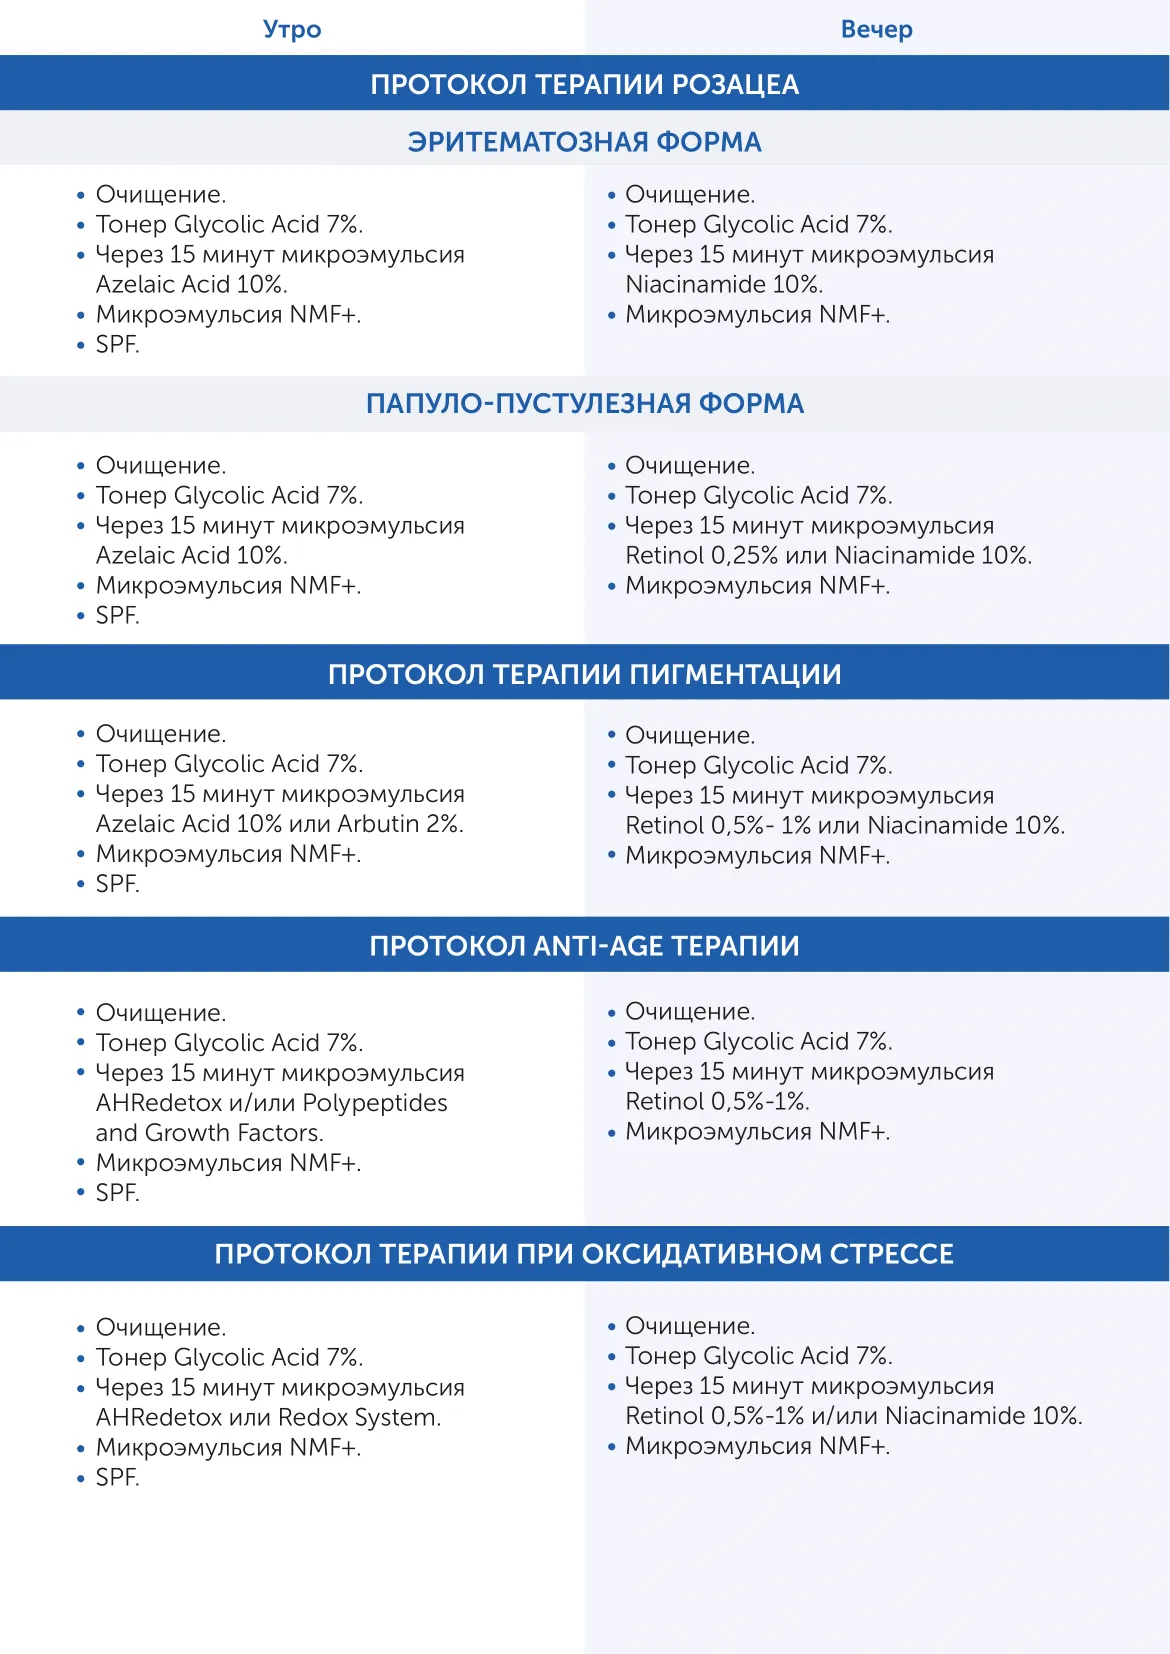

АУРИН - агентство правильных брендов, объединяющее специалистов и производителей индустрии красоты

Микроэмульсия на основе транс-ретиноевой кислоты Retinol 0,25% Skintellectual Solutions

Ретинол 0.25% (технология Hyalosphere)

AQUA

SODIUM HYALURONATE

PHENETHYL ALCOHOL

CAPRYLYL GLYCOL

AMMONIUM ACRYLOYLDIMETHYLTAURATE/VP COPOLYMER

PARFUM

RETINOL

CITRIC ACID

BHT

BHA

Возрастные изменения, нарушение пигментации кожи

Описание

Микроэмульсии Skintellectual Retinol, в основе которых лежит транс-ретиноевая кислота, по-настоящему преображают кожу. Их эффективность в борьбе с морщинами, угревой болезнью и пигментацией – медицинский факт. Максимально результативное действие микроэмульсий основано на запатентованном способе доставки Hyalosphere™, что дает им более глубокое пронивкновение в кожу и более длительное сохранение высокой концентрации активного ингредиента (до 6 часов). Компонент

проникает в глубокие слои кожи, деликатно устраняя возрастные

проблемы разглаживает морщины, осветляет пигментные пятна,

выравнивает тон и текстуру кожи,а разное процентное содержание ретинола (от 0,25% до 1%) в микроэмульсии позволяет минимизировать риск нежелательных реакций. Требуется консультация дерматокосметолога.